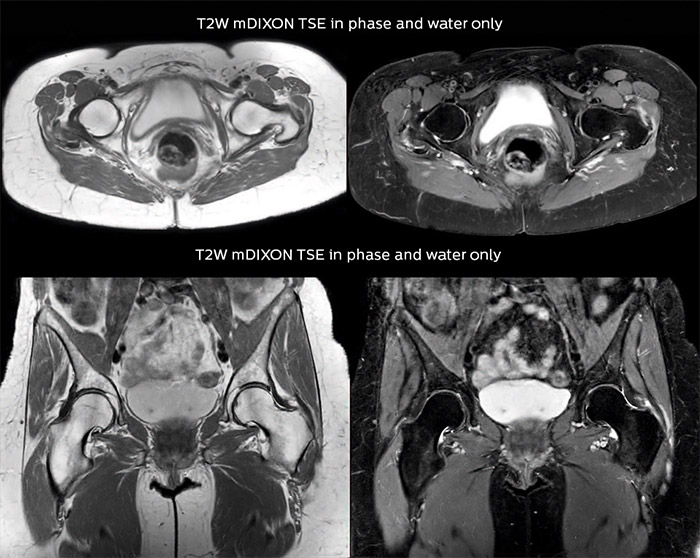

“For bone assessment near joints, mDIXON TSE provides the visualization and multiple contrasts to describe abnormalities within a limited number of acquisitions. Bone marrow signal abnormalities are common MRI findings that can represent various underlying causes, from normal variance to malignancy. So, it is important for us to notice and characterize these findings. With different contrasts, both with and without fat signal as mDIXON TSE efficiently provides, we can make a confident diagnosis.” “Other examples in bone are the signal description of a necrotic fragment in osteonecrosis, the signal description of tumoral matrix that has different components (necrosis, hemorrhage, cartilage, bone formation). These are all possible thanks to in-phase and water images from a single mDIXON acquisition.”

Fat suppressed images appear homogeneous over the entire image, even with large coverage at 3.0T – for instance in scapular or hip girdles – or in the bearing areas or around metal prostheses, where fat suppression is often deficient with STIR or spectral fat suppression, causing diagnostic difficulties. If a diagnostic image is right the first time, we don’t need to repeat or add a sequence.” “mDIXON TSE sequences allow simultaneous characterization of morphological changes from the in-phase T2-weighted images and visualization of edematous changes, thanks to the water T2-weighted images from the same acquisition. Anatomical and morphological considerations could be a partial or complete ligament tear, a bony avulsion or hematoma.” “For soft tissue assessment mDIXON brings similar benefits. For example in one T2-weighted mDIXON TSE acquisition, having the multiple contrasts helps us assess abnormalities in peripheral nerves fascicles, which may be due to anatomical or inflammatory changes..”

Dr. Lefebvre appreciates the efficiency of mDIXON TSE. “Using mDIXON TSE we can reduce the number of sequences scanned, without reducing the number of contrast types provided. In addition, we also value the reduction we see in repeats because of artifacts (as frequently found in other fat suppressed sequences as SPAIR and SPIR), making the acquisition non-diagnostic. Imaging right the first time is the most efficient way for us, and also for the patient.” “Using mDIXON TSE gives us homogeneous fat suppression in a reduced scan time, as well as good correlation between different images. In addition, we have a direct match between different contrasts because they are obtained from the same acquisition.”